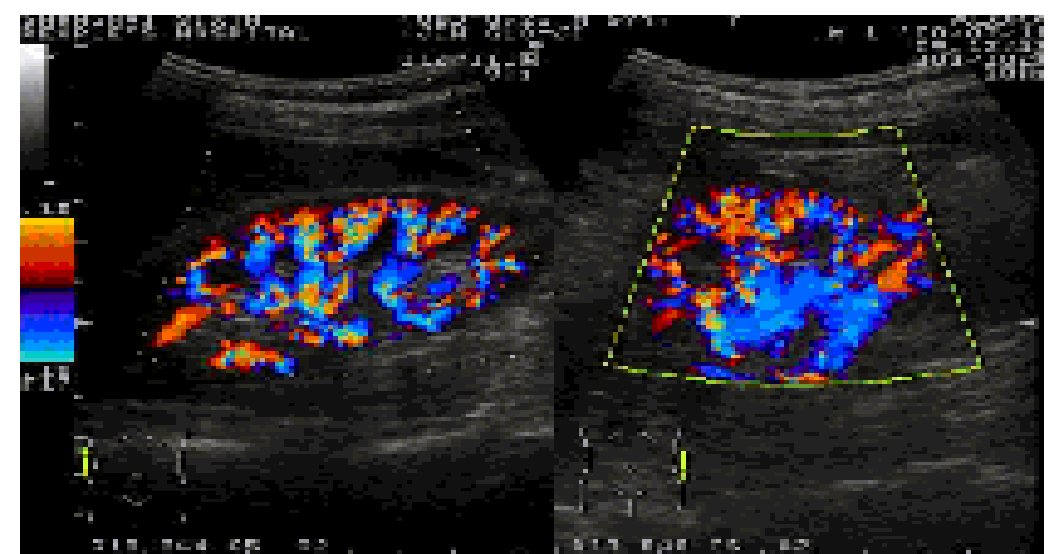

第五节 彩色多普勒

一、CDFI信号输出

红色:正向流

蓝色:反向流

绿色:紊乱程度

二、与频谱多普勒的对比

1、频谱多普勒:定量

彩色多普勒:定性

2、频谱多普勒:不直观

彩色多普勒:直观